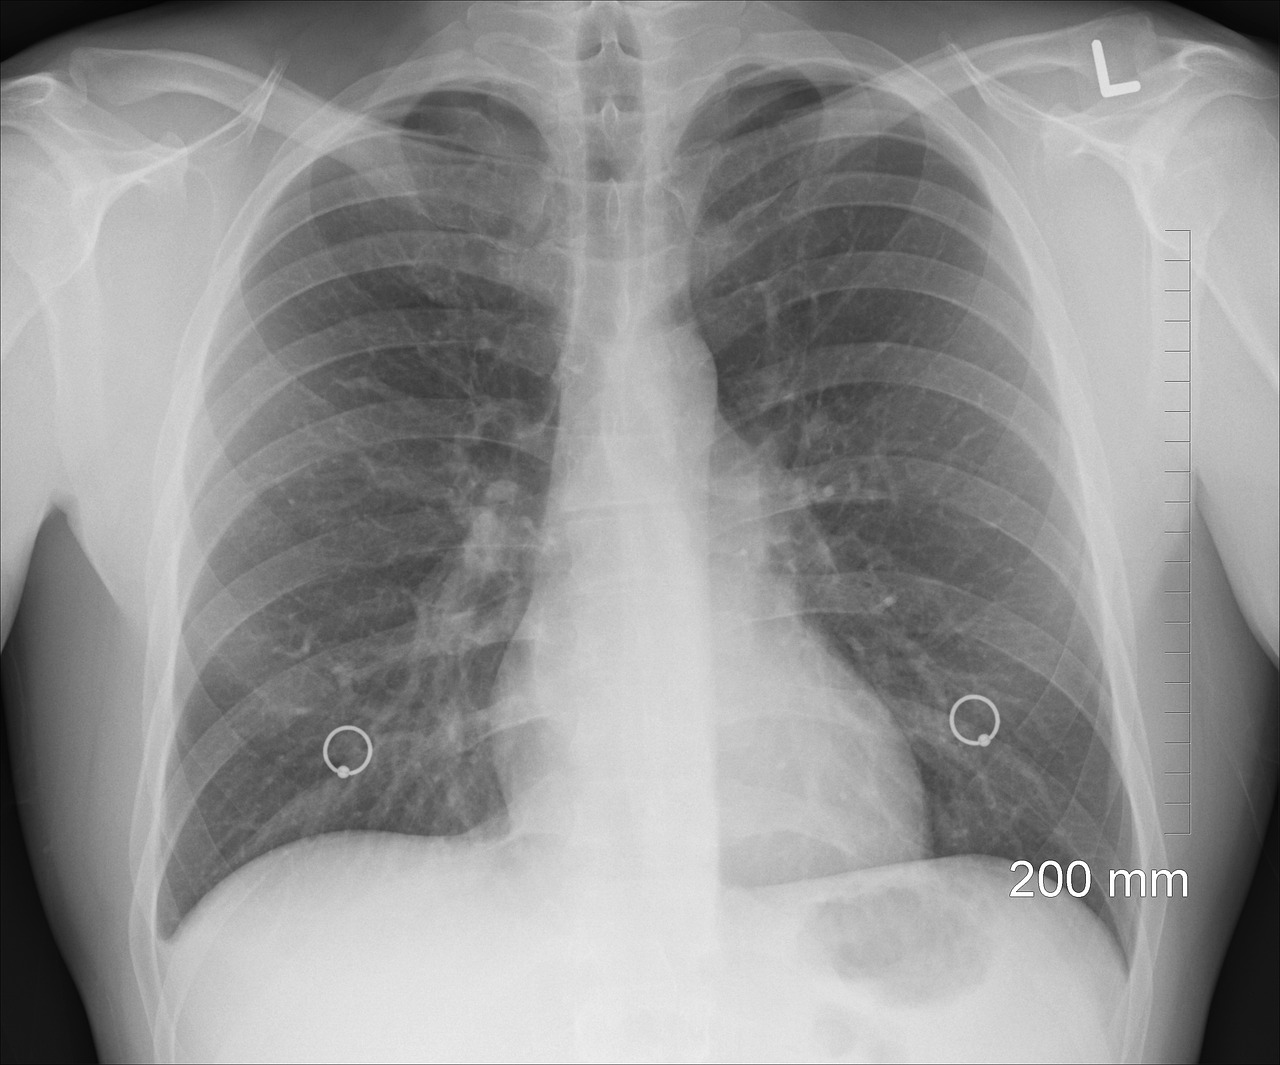

2) 영상 검사

- X-ray 촬영 : 폐결절의 초기 발견을 위한 기본 검사입니다.

- CT 스캔 : 더 정밀한 이미지를 제공하여 결절의 크기, 모양, 위치 등을 평가합니다. 필요에 따라 고해상도 CT가 사용될 수 있습니다.